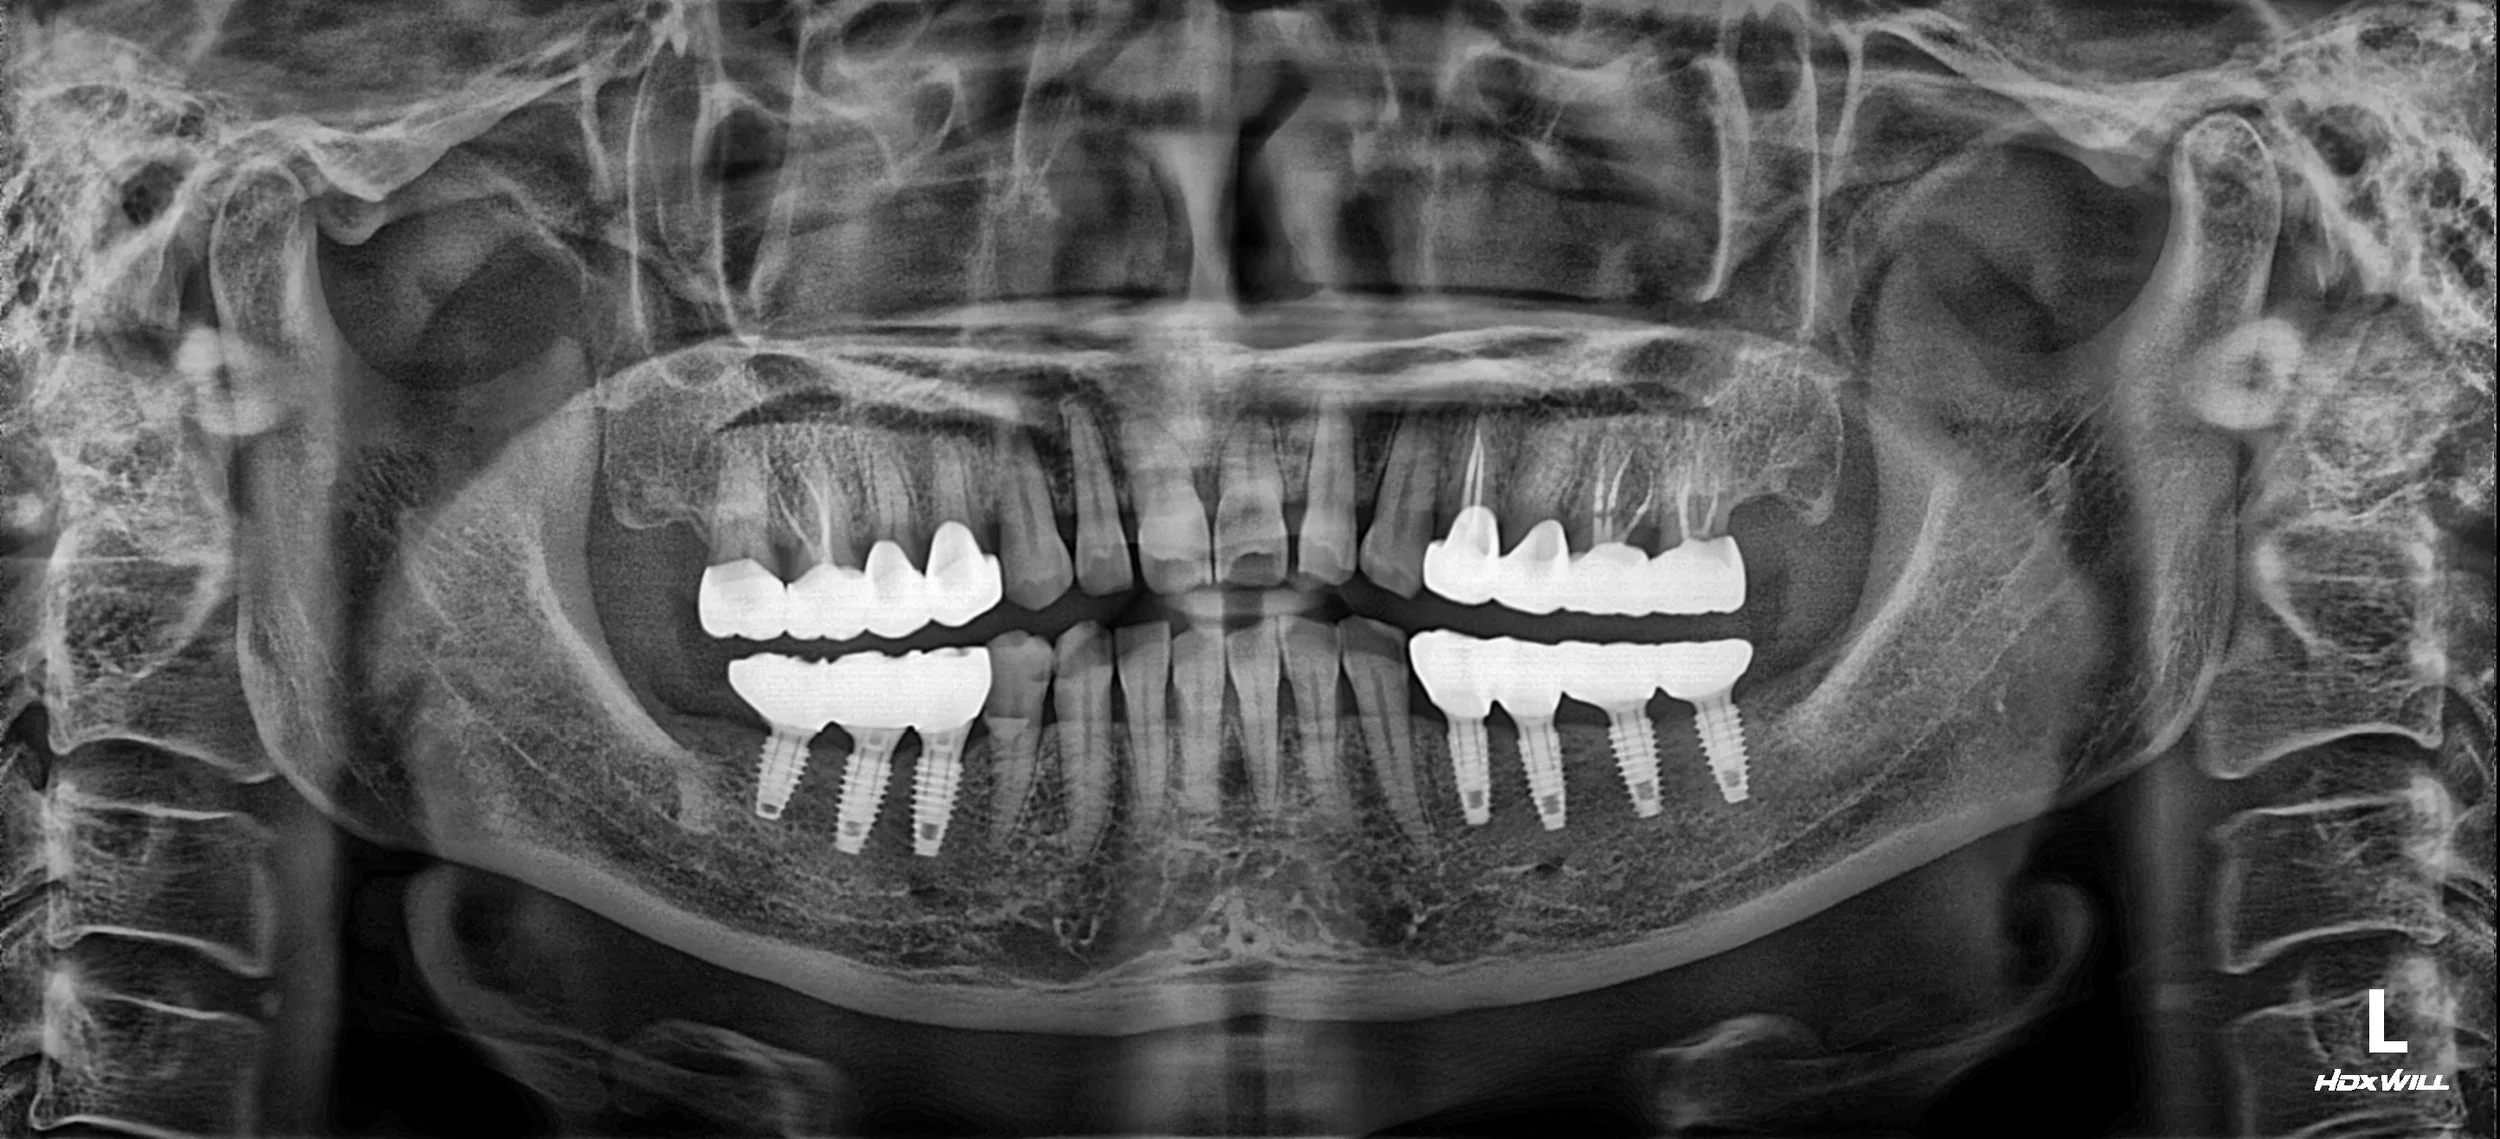

1. Implant-Based Reconstruction: Dental implants were strategically placed in the posterior regions of both arches to restore missing units and provide robust vertical support.

2. Occlusal Plane Engineering: The new posterior restorations were meticulously designed to correct the previously uneven occlusal plane. By establishing an ideal occlusal curve, we redistributed the biting forces, effectively protecting the anterior teeth from the excessive loads they had been bearing.

3. Functional Harmony: The intermaxillary relationship was improved by providing stable posterior stops at an optimized vertical dimension. This alignment allowed for a more comfortable and physiologically sound mandibular position.